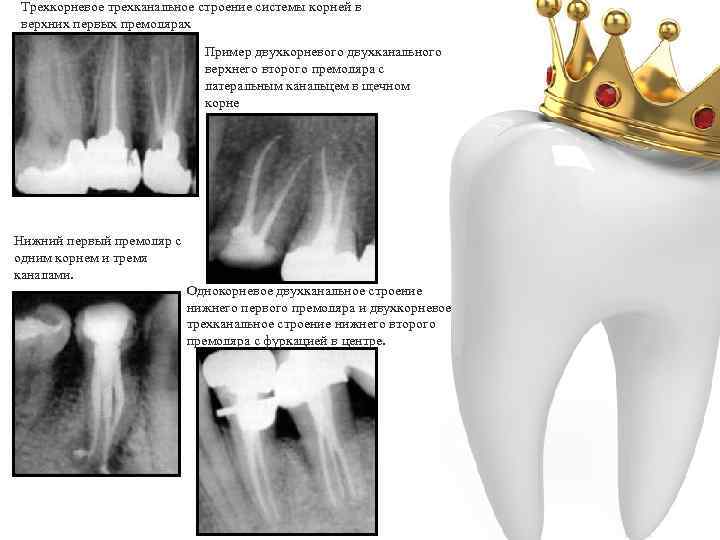

Трехкорневое трехканальное строение системы корней в верхних первых премолярах Пример двухкорневого двухканального верхнего второго премоляра с латеральным канальцем в щечном корне Нижний первый премоляр с одним корнем и тремя каналами. Однокорневое двухканальное строение нижнего первого премоляра и двухкорневое трехканальное строение нижнего второго премоляра с фуркацией в центре.